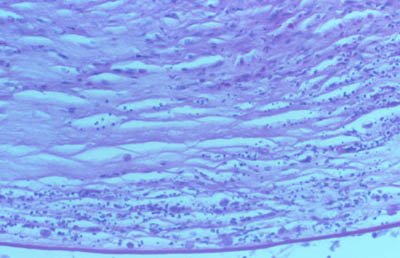

Tejido corneal Procesado

DH&E

H&E

PAS

CW